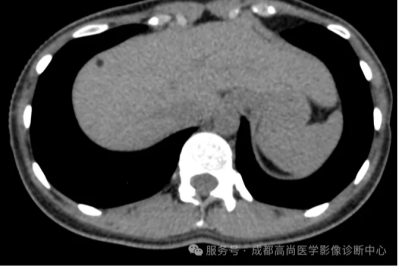

18F-FDG PET/CT 显像在乳腺外 Paget 病诊疗中的关键作用